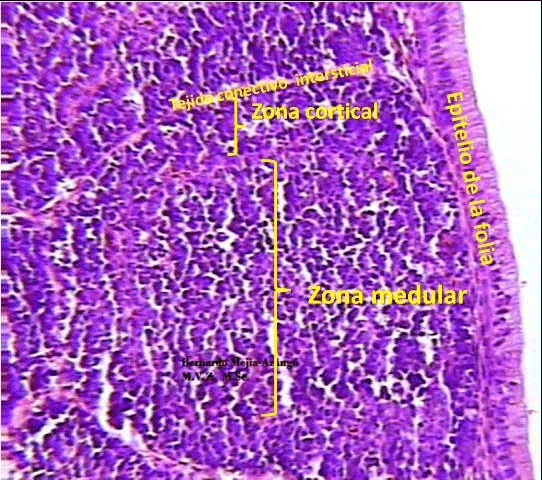

Enfermedad de Gumboro: depleción linfoide y lesiones atróficas, pueden ser inducidas por las vacunas? - Image 3

Imagen No. 3 Dos folículos linfoides de bolsas de Fabricio (Hematoxilina-Eosina 40 X) de dos pollos de 31 días de edad, una normal (Izquierda) y una depletica +++ (Derecha). Los grados de depleción se califican en un forma subjetiva (La que depende de la experiencia) en diferentes escalas de acuerdo con el patólogo. La escala de +, ++, +++ y ++++ es común en Colombia, al menos en el Valle del Cauca. Pude haber otras escalas, creo que hay una que va de 1 a 7.